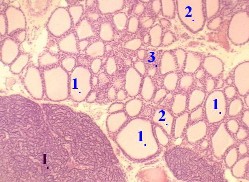

1. а) Основная часть железистых клеток щитовидной железы образует многочисленные фолликулы (1). б) Последние заполнены гомогенным коллоидом(2). 2. Небольшая часть железистых клеток формирует компактные скопления вне фолликулов - т.н. экстрафолликулярный эпителий (3). 3. При этом надо иметь в виду, что на препарате некоторые из таких "экстрафолликулярных скоплений" железистого эпителия могут на самом деле принадлежать фолликулам, срезанным вдоль их стенки. 4. На приведённых снимках в поле зрения находится также околощитовидная железа (I). | 3,а-б. Препарат – щитовидная железа. Окраска гематоксилин- эозином. Полный размер Полный размер |

II. Межфолликулярные прослойки соединительной ткани

а) Между фолликулами проходят тончайшие прослойки соединительной ткани (4). Они содержат ф енестрированные кровеносные капилляры, которые покрывают до 50% поверхности фолликулов; более крупные кровеносные сосуды (6), сеть широких лимфатических капилляров | |

и вегетативные нервные волокна – в основном, постганглионарные волокна симпатической нервной системы. б) Заметим: стимуляция последних усиливает секрецию гормонов в кровь, но значительно слабее, чем действие ТТГ (тиреотропного гормона гипофиза и эпифиза). |